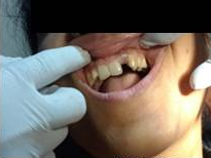

After Placement of Prosthesis

Single Tooth Implant

Post Operation